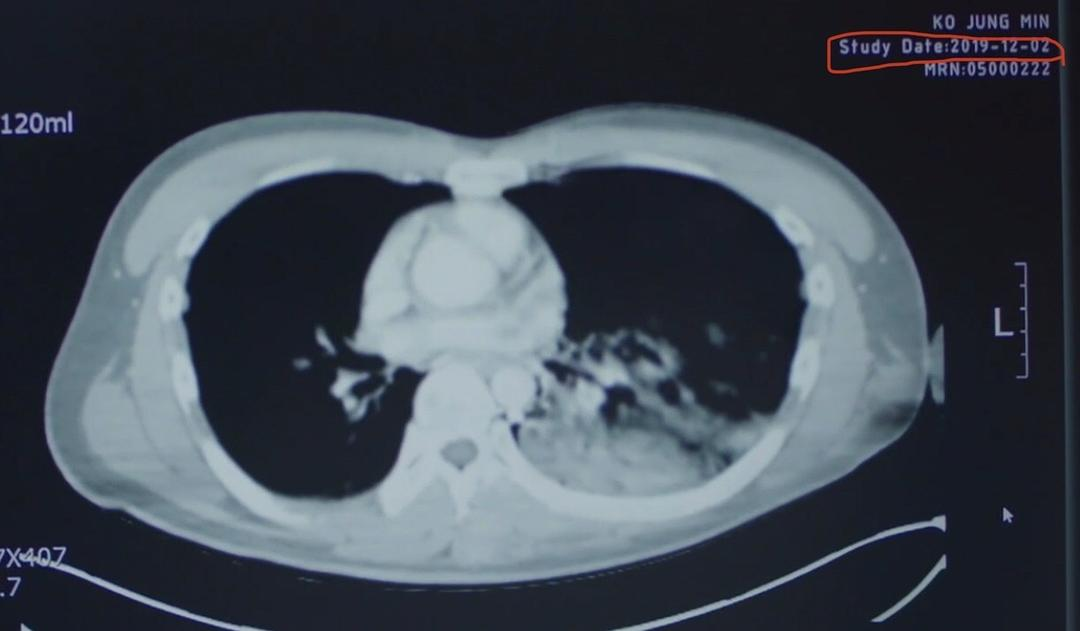

2019年12月2日,星状细胞瘤,三年前做过手术,复发